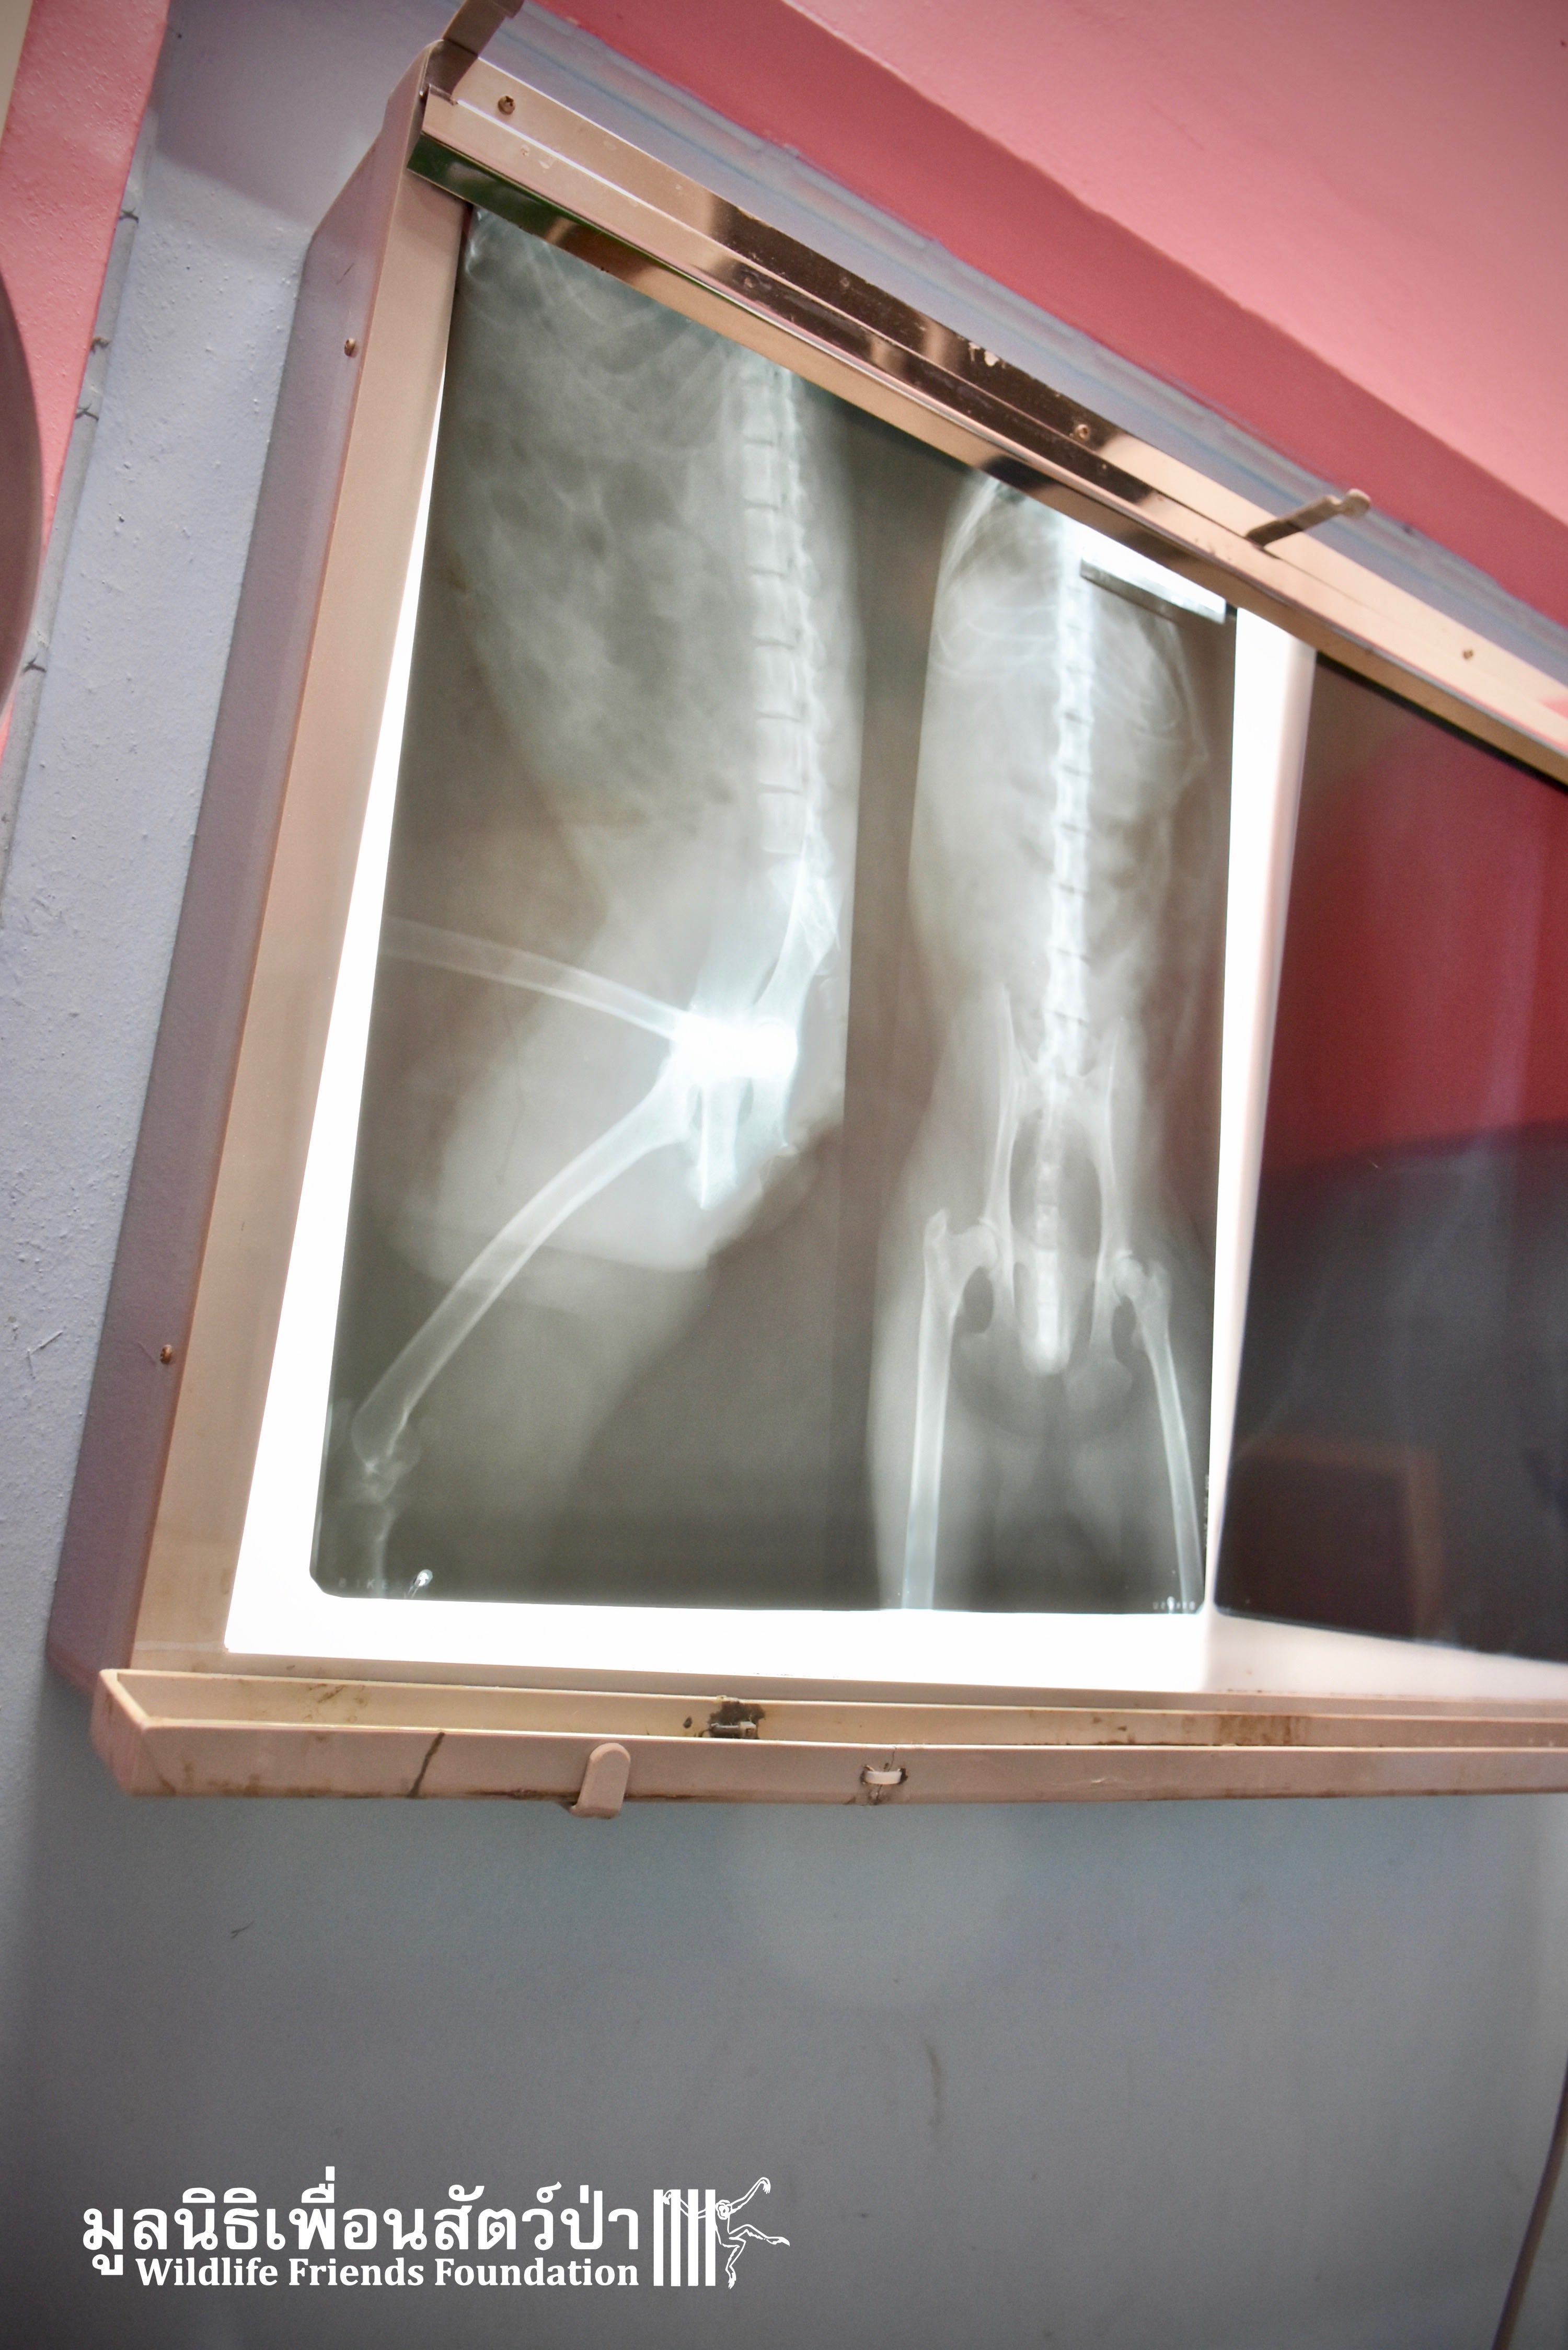

At their arrival, it is a half-paralyzed old monkey that the WFFT Team faced. The long-tailed macaque (who do not have any tail by the way, and who has been called Hang Kud for that reason) was unable to move his lower limb from the hip. Hang Kud was not receptive to any stimulation on his feet, however, he didn’t have any wounds. He was taken to a veterinary clinic to perform an x-ray. To do so safely, Hang Kud was sedated. Luckily, the x-ray revealed nothing was broken!

Once the Rescue Team came back at the center, the Vet Team performed full health check. The condition of his teeth indicates that he his rather old. Generally he is in good physical condition. For this reason, and regarding the x-ray, the theory of a car accident was less and less considered as an option. It could be a spinal problem that did not appear on the x-ray or even a birth defect.